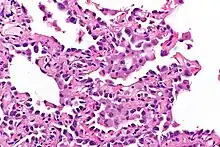

Microscopy

- Well-demarcated, nodular lesions ranging 2–5 mm in pulmonary parenchyma.

- Type II pneumocytes without nuclear atypia lined thickened alveolar septa and proliferated papillary structures.

- Enlarged cuboidal cells lining mildly thickened alveolar septa.[11]

- Enlarged cuboidal cells have abundant, eosinophilic cytoplasm and large, round nuclei.[12]

- Papillary pattern with irregular margin and lymphocyte infiltration in the stroma.[13]

- No proliferation of immature smooth muscle cells suggestive of lymphangioleiomyomatosis.